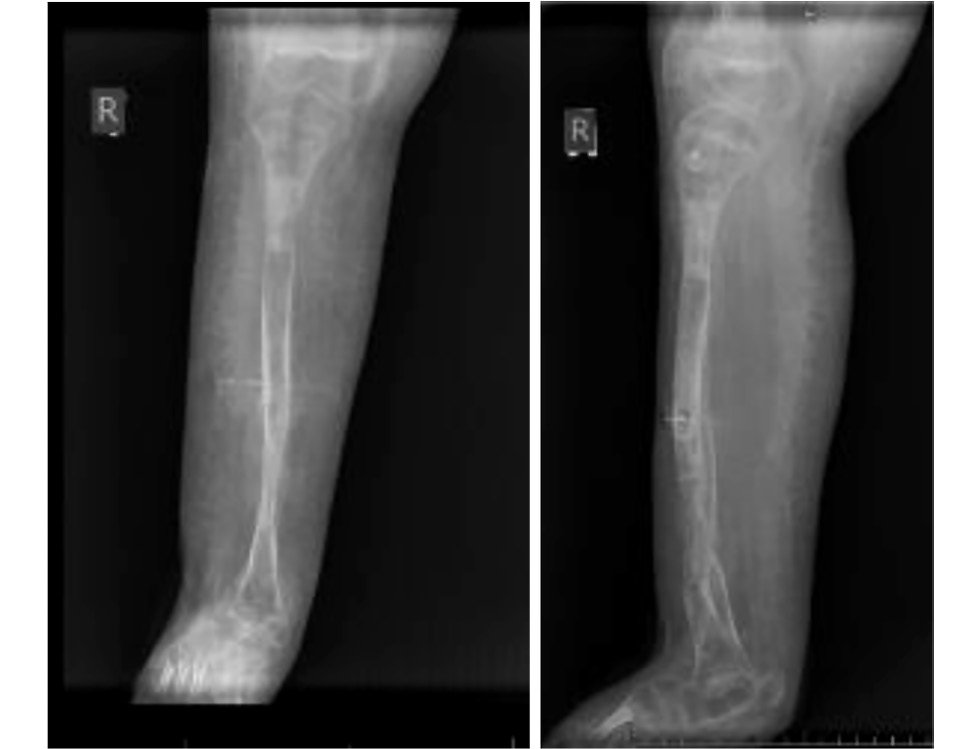

The patient underwent a comprehensive assessment, including clinical and radiographic evaluation. Functional activity was assessed using the Gillette questionnaire [19], along with evaluation of pain, satisfaction with limb function, and esthetic appearance. The patient exhibited a marked shortening (10 cm) of the right lower limb (Fig. 1). A fibrous remnant of the fibula was palpable, and radiographs revealed complete absence of the fibula, as well as tarsal coalition, and multicomponent deformity of the right foot: equinus of 110°, arch angle of 145°, hindfoot valgus of 20°, and forefoot abduction of 35° (see Fig. 1). The patient was only able to move independently within a 5-meter room using crutches or by crawling, bearing weight on the left lower limb. Due to the pronounced shortening, weight-bearing on the right lower limb was not possible. Fibular hemimelia was classified as type II according to Achterman and Kalamchi [20], type 2 according to Aranovich [21], and type 3C according to the classification by Paley [4]. Laboratory results, including blood and urine tests, were within normal limits.

Fig. 1. Photographs (a) and radiographs (b) of the lower limbs before treatment.